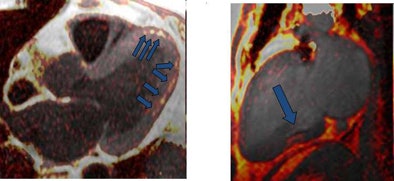

| Above, four-chamber, three-chamber, and short-axis images of a patient with fat deposition in segments of myocardial infarction. Precontrast fat-water separation imaging shows midwall fat deposition that is hyperintense in fat images and hypointense in water images. Late gadolinium-enhanced (LGE) infarct imaging shows an apical-septal chronic myocardial infarction. Below, fat-water separation imaging color overlay. Colored fat displayed on grayscale water images from two patients with chronic myocardial infarctions. Arrows point to midwall fat deposition. Images courtesy of Dr. James Goldfarb. |

The study examined 25 patients with LV MI (mean age, 64.3 years; range, 43.2-82.1 years) using a 1.5-tesla MRI scanner system. Protocols included volumetric cine, fat-sensitive, and late gadolinium-enhanced (LGE) infarct imaging. Water-fat separation was performed by using a three-point Dixon reconstruction from in- and opposed-phase black-blood gradient-echo images.

Fat deposition was seen in 68% of patients in areas of chronic MI. Patients with fat deposition on imaging had larger infarctions (30.0 mL ± 15.1 [standard deviation] versus 14.8 mL ± 6.1; p = 0.002), less wall thickening (2.3% ± 20.0 versus 37.8% ± 34.4; p = 0.003), and impaired endocardial wall motion (2.9 mm ± 2.0 versus 5.8 mm ± 2.6; p = 0.007) compared to normal patients, the group reported. In addition, the volume of fat deposition correlated with infarct volume, LV ejection fraction, LV end-diastolic volume index, and LV end-systolic volume index.

"Since fat deposition was found solely in myocardial segments with or directly adjacent to MI, one might infer that LV MI is a precursor to LV myocardial fat deposition," Goldfarb and his team wrote, adding that serial imaging over several years would be necessary to test the hypothesis. "We also found that fat deposition was predominately midmyocardial or midepicardial, whereas results of prior autopsy and CT studies suggest that fat deposition almost always affects the subendocardium."